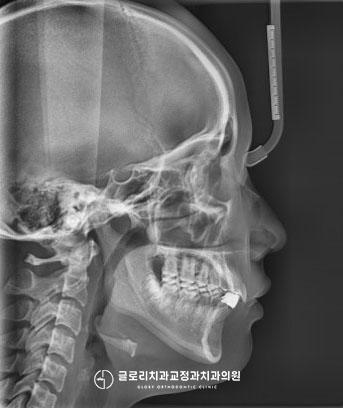

아래 앞니 쪽을 주목해 주시면

간격이 촘촘하지 않고

넓은 유격을 보이는데요.

전치부의 개수는 아래위 6개씩으로,

중절치, 측절치, 견치

세 부분으로 나눠집니다.

그러나 이 환자의 경우에는

위의 전치부에는 6개 모두 있지만,

하악에서는 4개만 잔존해 있는데요.

하악을 기준으로

43 42 41 | 31 32 33

으로 보시면 이해에 도움이 됩니다.

이 환자께서는

32번과 42번이 결손된 상태입니다.